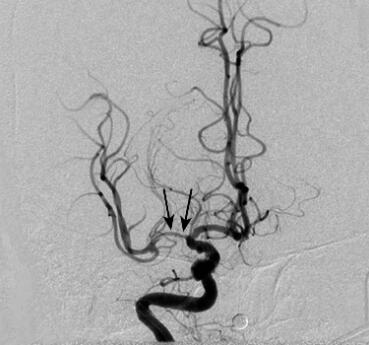

右大脑中动脉狭窄动脉球囊扩张术(2011年6月9日):术后造影见右侧大脑中动脉M1狭窄部位有所扩张(图2)。

图2 大脑中动脉球囊扩张术后DSA结果:右侧大脑中动脉狭窄部位有所扩张(箭头)